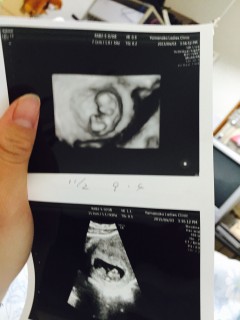

手と足が生えて2頭身のまるで ドラえもん姿! うぅ~可愛すぎるぅ!!! 予定日確定★二週間後初健診★ 早く動いてるところ見たい!!! 悪阻ピーク気合で乗り切るぞぉ(T.T)

可愛い二頭身(笑)手と足がわかるようになり、人らしい形に! 横向きでねんねしてました。 この日、母子手帳の交付手続きを行いました。母子手帳を手にして、更に実感!